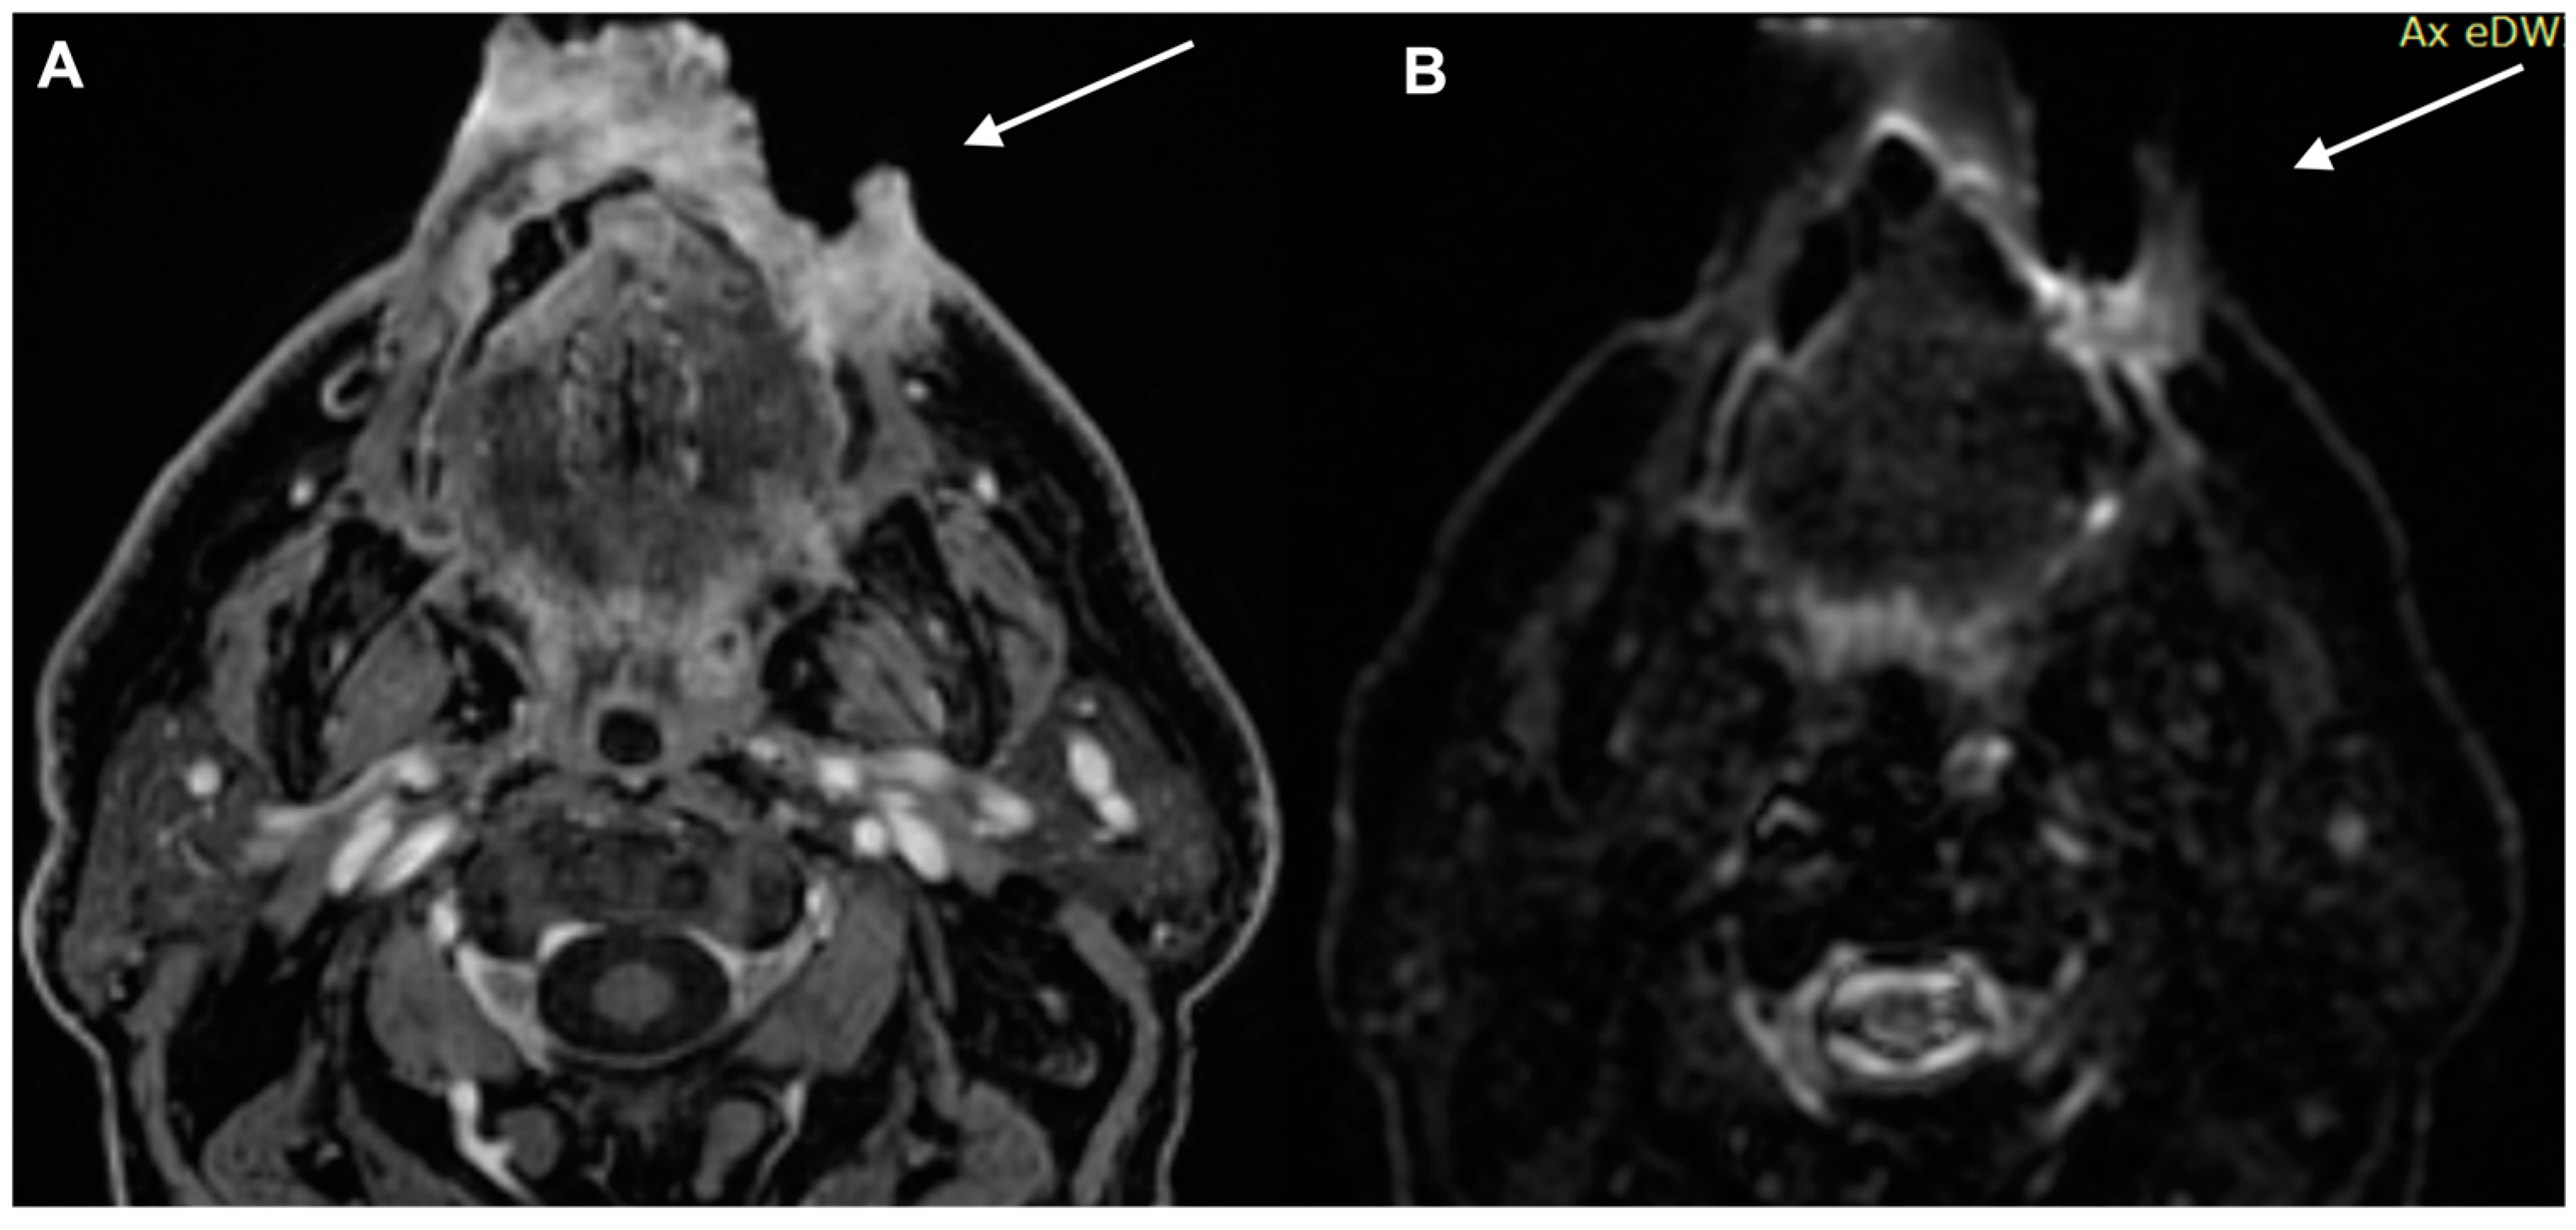

2. Diagnostic Imaging and Non-Melanoma Skin Cancer

3. Diagnostic Tools and Non-Melanoma: Staging and Surveillance